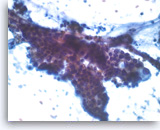

Ductal adenocarcinoma #1,

Pancreas FNA, Cell Block.

The tumor cells are pleomorphic and form poorly organized glands of variable sizes. Some of the glands are fused together. Prominent intracytoplasmic mucin is present.

40X

Ductal adenocarcinoma #1,

Pancreas FNA, Cell Block.

The tumor cells are pleomorphic and form poorly organized glands of variable sizes. Some of the glands are fused together. Prominent intracytoplasmic mucin is present.

40X